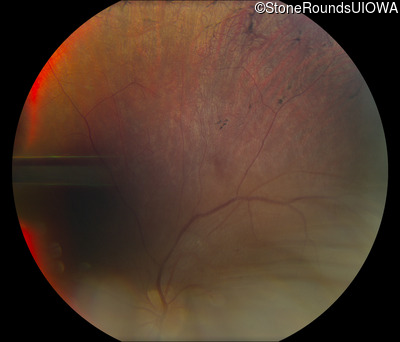

Fundus Photography - Right - 20/30 -2

Exemplar